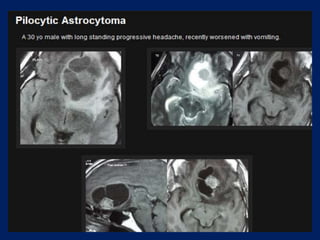

Pilocytic astrocytoma